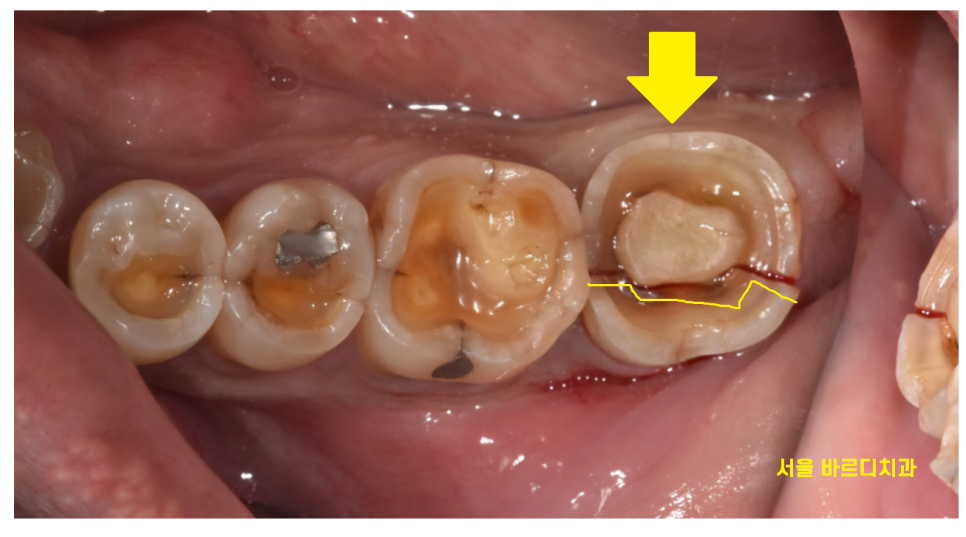

그리고 정확히 6개월뒤

환자분께서 망월동 치과를 다시 방문하셨습니다.

이가 갈라진것 같아요

23.10.16

네...

이가 반으로 갈라졌습니다.

이런 불상사를 방지하기 위하여

신경치료 후 보철을 해야한다고 말씀드리는거에요.

결국 이가 반으로 갈라져서

환자분은 발치 후 임플란트 치료를 진행하셨답니다.